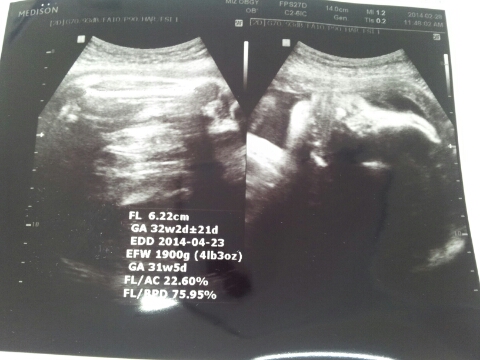

퐁이 32주 3일째, 잘지내고 있어요~

퐁이가 와줘서 좋았던게 엊그제같은데 벌써 우리 둘째아드님 김퐁군은 32주하고도 3일째 몸...